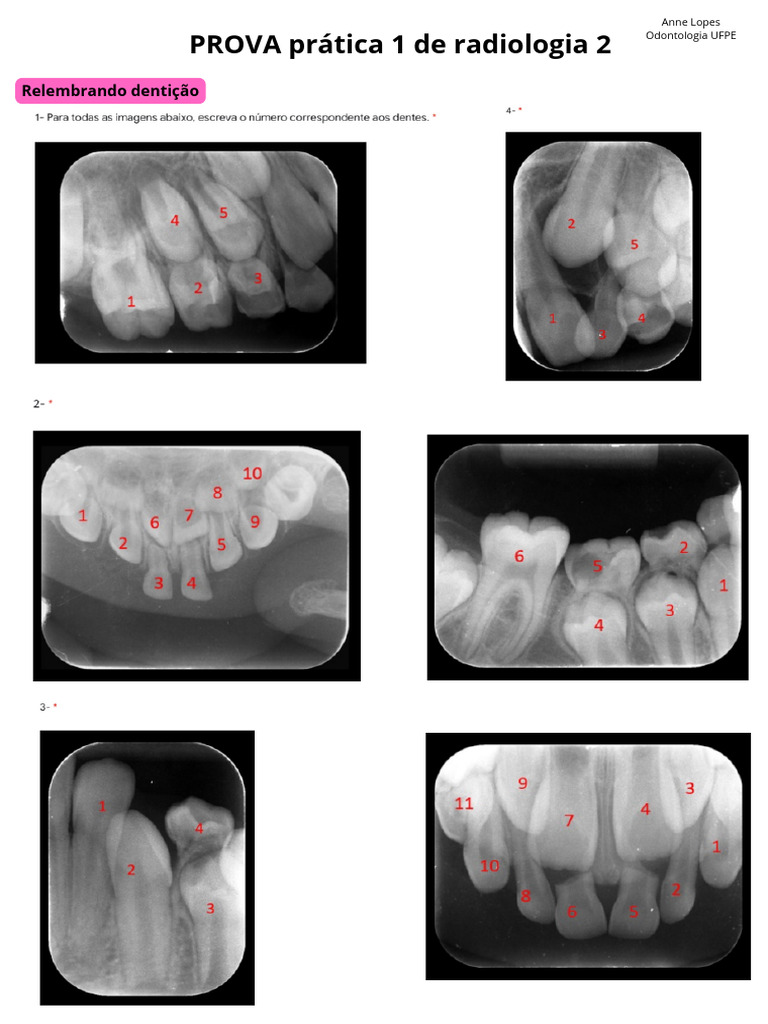

Relato de osteomielite esclerosante difusa em paciente diabético Report of diffuse sclerosing osteomyelitis in a diabetic patie

image size: 1191x1684